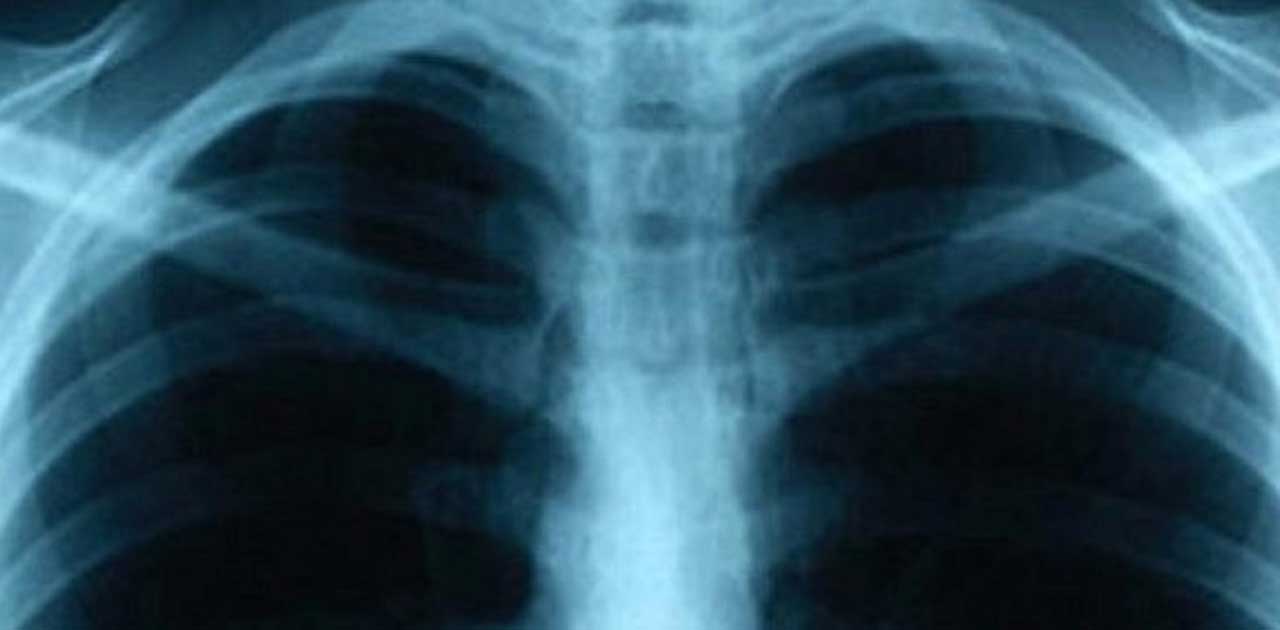

इस दौरान अश्विनी कुमार चौबे ने कहा कि भारत सरकार ने साल 2025 तक भारत को टीबी मुक्त बनाने का लक्ष्य तय किया है. उन्होंने कहा कि हमने पोलियो मुक्त भारत बनाया है, तो टीबी मुक्त भारत भी बनाएंगे और सरकार उसी दिशा में आगे बढ़ रही है.